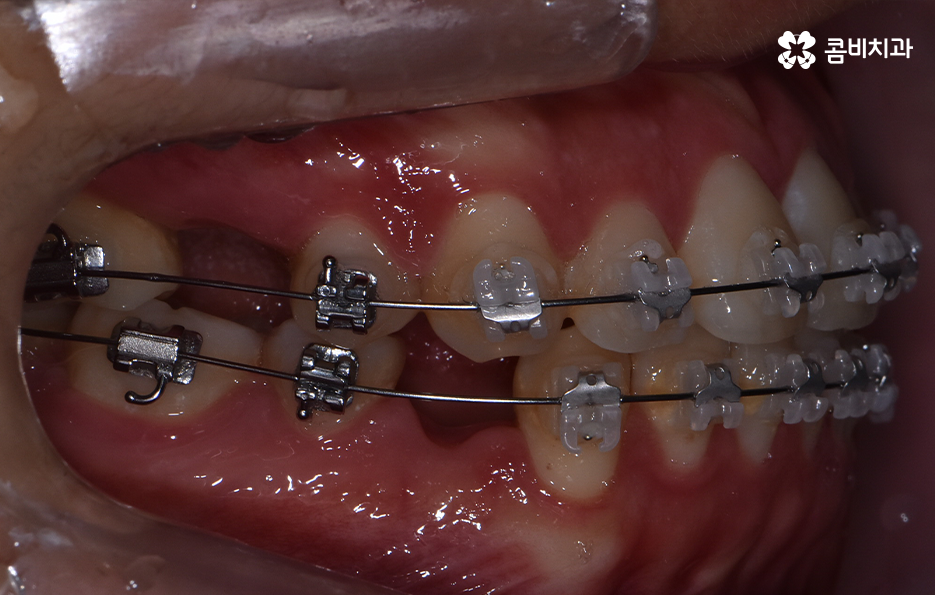

오늘은 돌출입발치교정 통해서 치열도 가지런하게 교정하고 얼굴형의 변화뿐 아니라 교합까지 잘 맞물려서 건강하게 치아교정을 하는 방법에 대해 알아볼 거예요

보통 치아교정을 통해 눈에 띄게 얼굴 변화를 느끼게 되는 경우는 쉽게 말해 발치를 통한 교정으로 볼 수 있어요. 그 이유는 치아를 발치하게 되면 발치한 만큼의 공간이 악궁에서 축소가 되기 때문에 그로 인해 얼굴라인이 갸름하게 변하게 되거나 돌출입발치교정 같이 돌출입의 개선이 되는 거예요

치아를 발치하고 이동하면서 얼굴 변화의 대표적 사례는 돌출입 개선이나 얼굴 라인의 변화뿐 아니라 얼굴 비대칭의 개선이나 팔자주름이 옅어지는 등의 변화를 꼽을 수 있어요